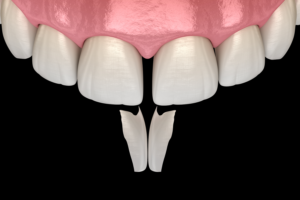

Günümüzde diş estetiği popüler hale gelmiştir. Bu amaçla yapılan uygulamaların bu üç amacı da yerine getirmesi mühimdir. Bu sebeple estetik amaçlı yapılan protezlerden önce mutlaka minimal invaziv(minimum müdahalecilik) yaklaşımların uygulanması gerekmektedir.

Zira bütün tıbbi uygulamalarda artık minimal invaziv yaklaşımlar ön plana çıkmaktadir. Bu sebeple dişlere sabit protez uygulamaları yapmadan önce diğer daha basit uygulamalar denenmelidir. Bunların hem geri dönüşü vardır hem de daha kolay ve ucuzdurlar. Bunlara örnek olarak gülüş tasarımında minik dişeti operasyonları, dişlerin renkli ve lekeli olmaları durumunda dolgu restorasyonları ve/veya diş ağartma uygulamaları kullanılanabilir. Bunlara hekiminizle ortak bir şekilde karar verebilirsiniz.